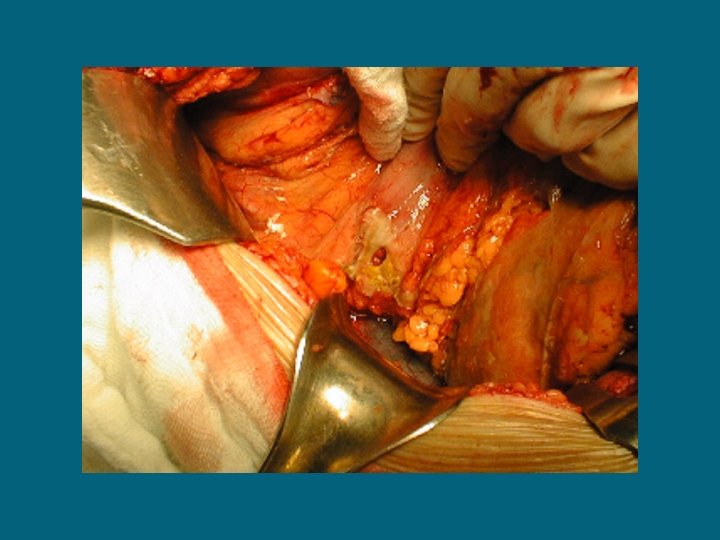

Peritonite diffusa purulenta

PERITONITI ACUTE DIFFUSE SECONDARIE A) PROCESSO PATOLOGICO (propagazione di processo infiammatorio o perforazione di organo cavo) : ulcera peptica perforata appendicite acuta colecistite acuta ischemia intestinale diverticolite neoplasia complicata pancreatite acuta altre

PERITONITI ACUTE DIFFUSE SECONDARIE B) TRAUMA (perforazione-rottura di viscere cavo)